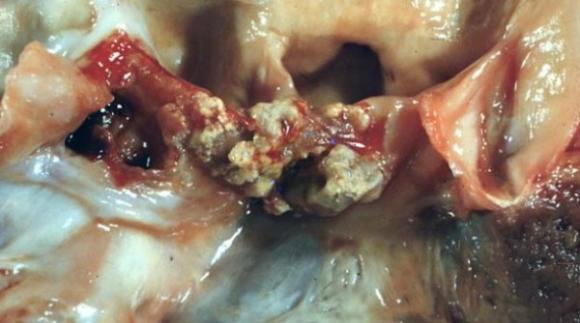

Científicos Argentinos de la UBA desarrollan un método para identificar las causas de una infección del corazón‏

Científicos de la UBA diseñaron una técnica para diagnosticar el origen de la endocarditis infecciosa. Esta enfermedad es producida por microorganismos que ingresan a la sangre durante intervenciones quirúrgicas y...